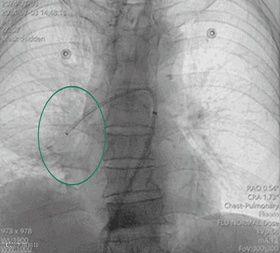

手术过程